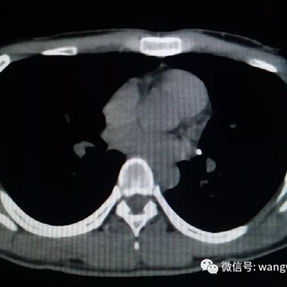

2. Improper bar Placement and Positioning: Preoperative imaging reveals that the bar was positioned along the upper edge of the groove-like depression and was placed at an angle.For optimal support and effective correction of the depressed bony structure, the bar should have been positioned at the base of the depression.